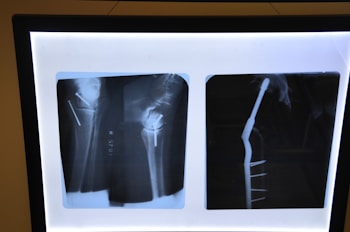

Precision Care for Complex Pelvic and Acetabular Fractures

Pelviacetabular Surgery

Our specialized Pelviacetabular Surgery service focuses on restoring stability and function after pelvic and acetabular fractures. Using advanced imaging and surgical techniques, we ensure precise alignment and faster rehabilitation for improved mobility and comfort.